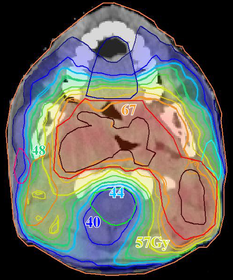

eam

A

ngle

O

ptimisation (

BAO

) in

I

ntensity

M

odulated

R

adiation

T

herapy (

IMRT

)